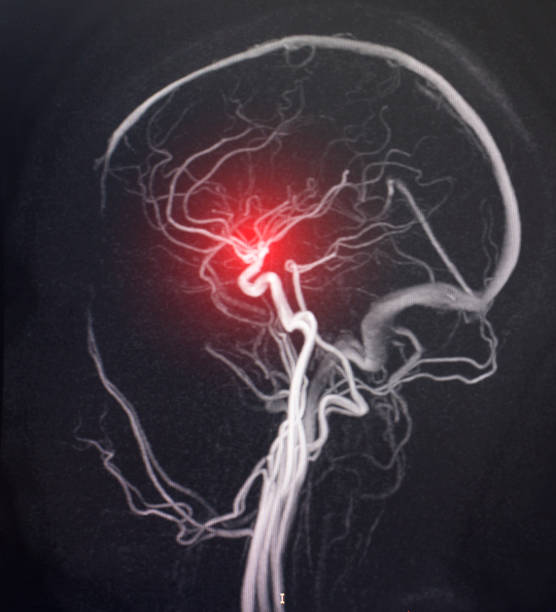

진단 방법은?

병원에서는 다음과 같은 검사를 통해 진단해.

- CT(컴퓨터 단층촬영) : 출혈 여부를 빨리 확인할 수 있어.

- MRI(자기공명영상) : 뇌조직의 손상 정도를 정밀하게 보여줘.

- MRA(자기공명혈관조영술) : 뇌혈관이 어디가 막혔는지 확인 가능.

- 경동맥 초음파 : 목 혈관 상태를 체크해줘.

- 심전도/심장초음파 : 심장에서 혈전이 생겼는지 확인해.

- 혈액검사 : 고지혈증, 당뇨, 염증 수치 확인 가능.

이런 검사는 발병 초기 몇 시간 안에 이뤄져야 하며, 치료 방향을 결정하는 데 핵심이야.